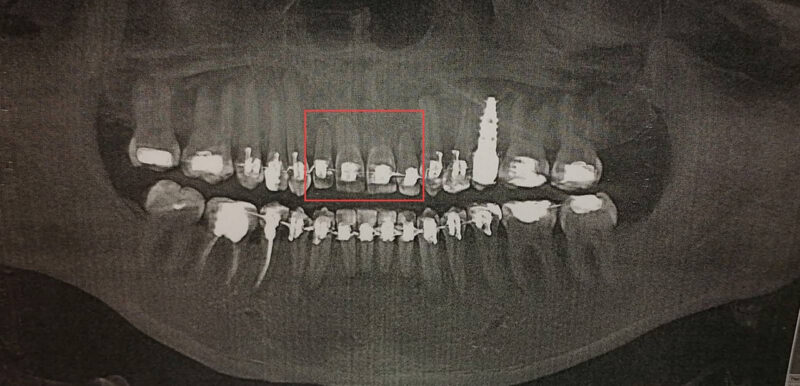

В 2024 году у неё заболел один из зубов. Сделали первый за всё время 3D-снимок, и выяснилось ужасное: корни четырёх передних верхних зубов почти рассосались. Брекеты с верхней челюсти сняли в августе 2024 года. Дома Юлия обнаружила, что один зуб уехал, появилась сильная щель между челюстями, прикус стал неправильным, а дикция нарушилась. Женщина написала жалобу руководству поликлиники и потребовала 7000 рублей компенсации морального вреда.

Суд назначил независимую судебно-медицинскую экспертизу. Эксперты подтвердили: лечение шло с нарушениями, рентгеновские снимки не делались вовремя, а после 2021 года лечение стало бесконтрольным. Услуга признана не соответствующей медицинским стандартам.